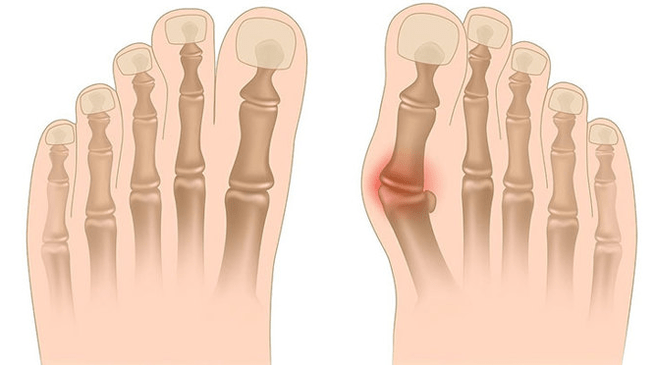

A deformação de Valgus é a curvatura do pé, caracterizada pelo achatamento de seu arco longitudinal. Normalmente, a borda interna do pé é reduzida ("gotas") e o calcanhar se desenrola.

Quando você pega os pés (se você os olhar por trás), uma deformação do tipo X é formada no nível do tornozelo: os tornozelos estão em contato, enquanto os saltos estão a uma distância de 5 a 6 centímetros um do outro.

No terceiro estágio, a protrusão do osso descongelado é determinado (notavelmente menor que o tornozelo na superfície interna do tornozelo), bem como um forte desvio do calcanhar externo (o paciente está baseado na borda interna do osso do calcanhar).

- A inspeção clínica, durante a qual o ortopedista detecta uma diminuição nos arcos do pé, o desvio dos ossos do calcanhar e do carneiro, o "desaparecimento" visível da externa e a protrusão dos tornozelos internos.